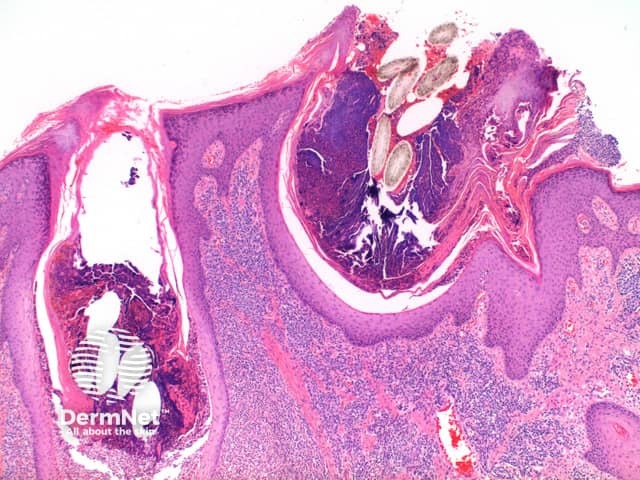

Low power view exhibits a dense superficial and deep inflammatory process with dermal scarring and follicular disruption (Figure 1). There may be variable degrees of overlying scale crust with tufted hair follicles evident as multiple hair shafts within widened follicular infundibulae (Figures 1 and 2). In the dermis are disrupted hair follicles with scattered naked hair shafts seen within a fibrotic dermis (Figures 2 and 3). There is a dense lymphoplasmacytic infiltrate with scattered neutrophils (Figure 4).

Figure 1